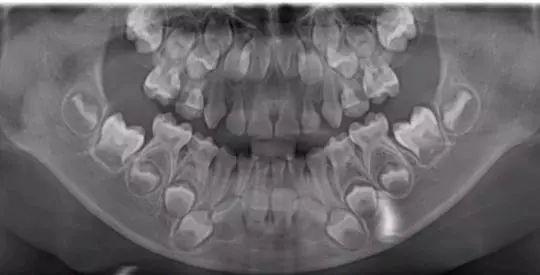

5岁的小朋友,画圈的是恒牙胚